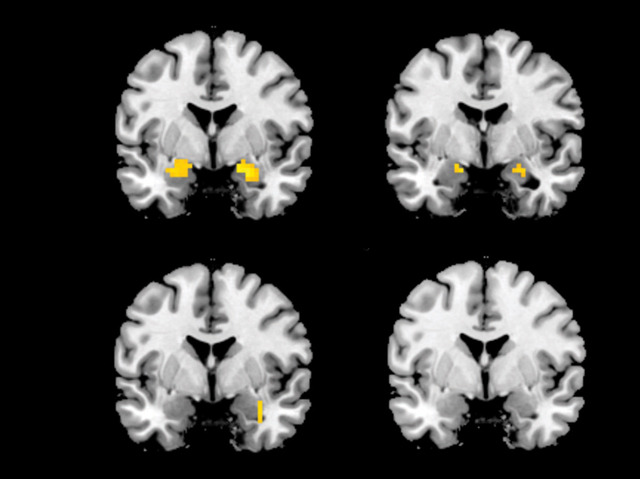

Stressful situations, such as war or accidents, leave behind mental as well as physical scars. When fearful memories surface again they can cause problems such as post-traumatic stress disorder (PTSD). Scientists have discovered that there is a crucial window in which painful memories can be altered and even erased altogether. Using lab simulations, researchers evoked fearful memories in two groups of volunteers. These scans reveal activity in a region of the brain called the amygdala, the seat of fear. The upper images are from volunteers recalling their fearful memory, showing strong brain activity in the amygdala (shown as yellow). The lower images are from volunteers who received a simple psychological treatment while recalling their fear. They show little or no activity, suggesting the fearful memories may have been wiped out. Although it's still experimental, this kind of approach could help to erase painful memories in the future.